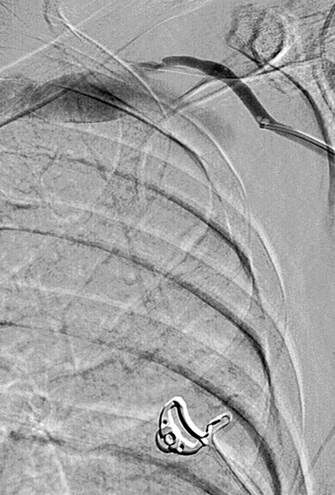

Injerto AV con trombosis y con estenosis en anastomosis venosas.

Catéteres DVX de AngioJet en injerto AV.

Imagen tras la activación del sistema AngioJet en el lado venoso del injerto AV.

Imagen tras la activación del sistema AngioJet en el lado arterial del injerto AV.